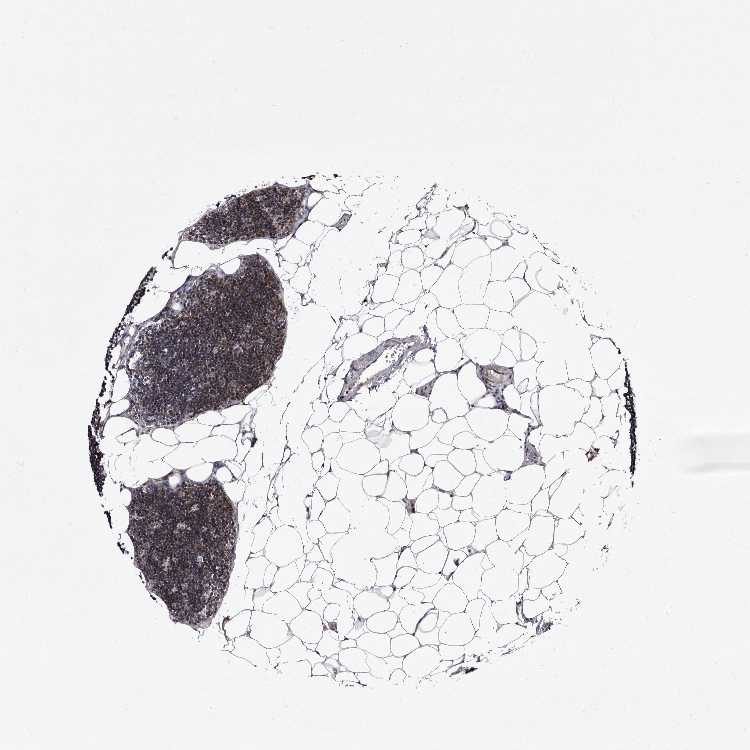

LYMPH NODE - Antibody stainingi

Antibody staining in the annotated cell types in the current human tissue is reported as not detected, low, medium, or high, based on conventional immunohistochemistry profiling in selected tissues. This score is based on the combination of the staining intensity and fraction of stained cells.

Each image is clickable and will lead to virtual microscopy that enables deeper exploration of all samples and also displays staining intensity scores, fraction scores and subcellular localization as well as patient and tissue information for each sample.

Antibody HPA025690

Germinal center cells Low

Non-germinal center cells Medium